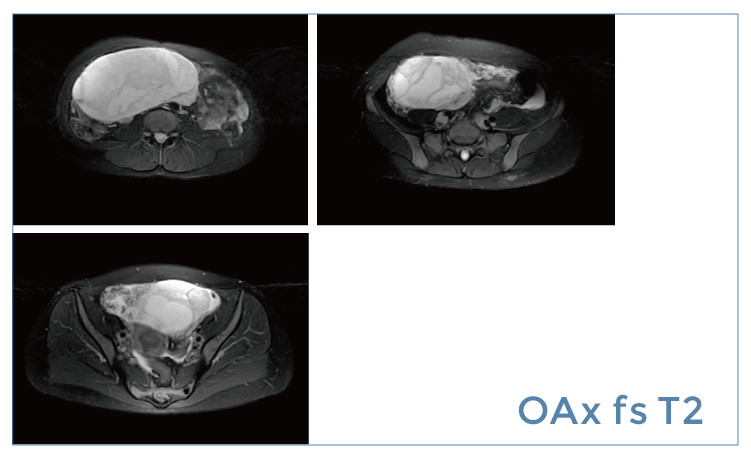

【朗润影像档案】20190419磁共振影像病例结果讨论

【朗润影像档案】磁共振影像病例分享(编号20190419)